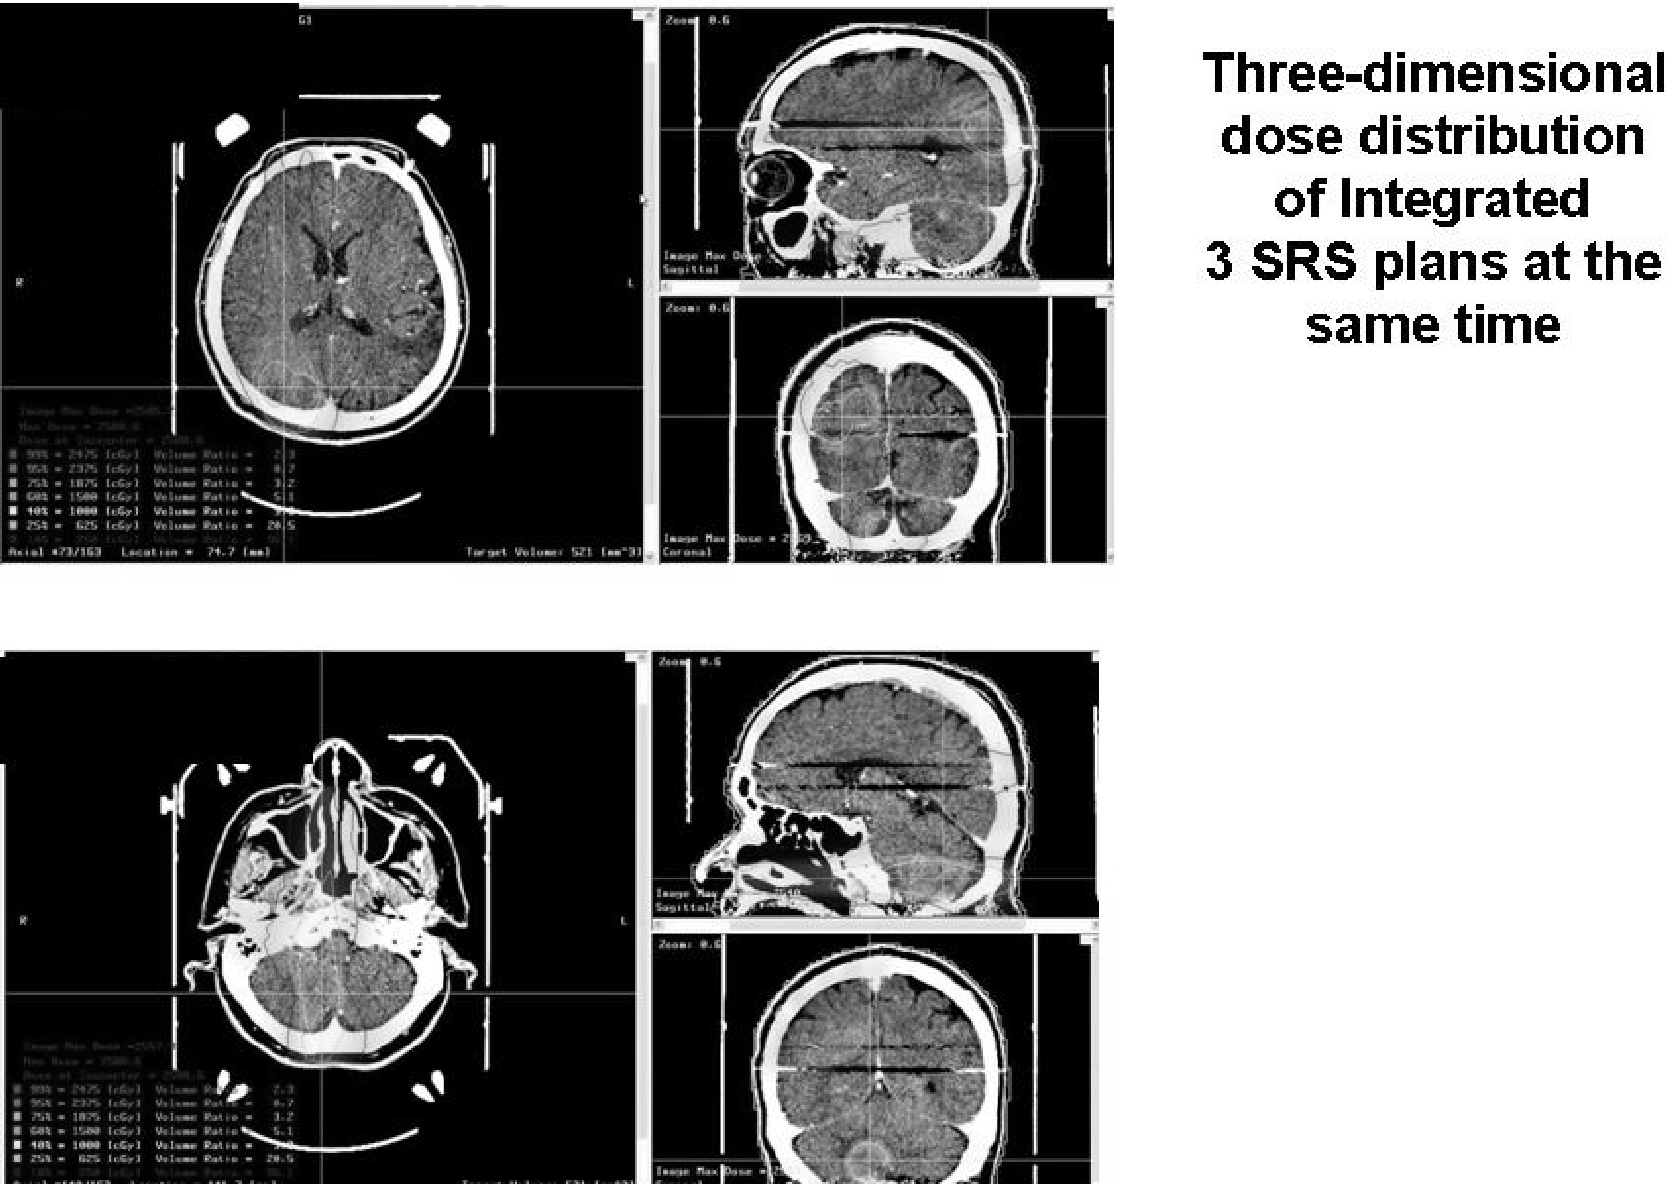

転移性脳腫瘍 Brain Metastasis 脳外科医 澤村豊のホームページ

転移性脳腫瘍 Brain Metastasis 脳外科医 澤村豊のホームページ

転移性脳腫瘍 Brain Metastasis 脳外科医 澤村豊のホームページ

転移性脳腫瘍 Brain Metastasis 脳外科医 澤村豊のホームページ